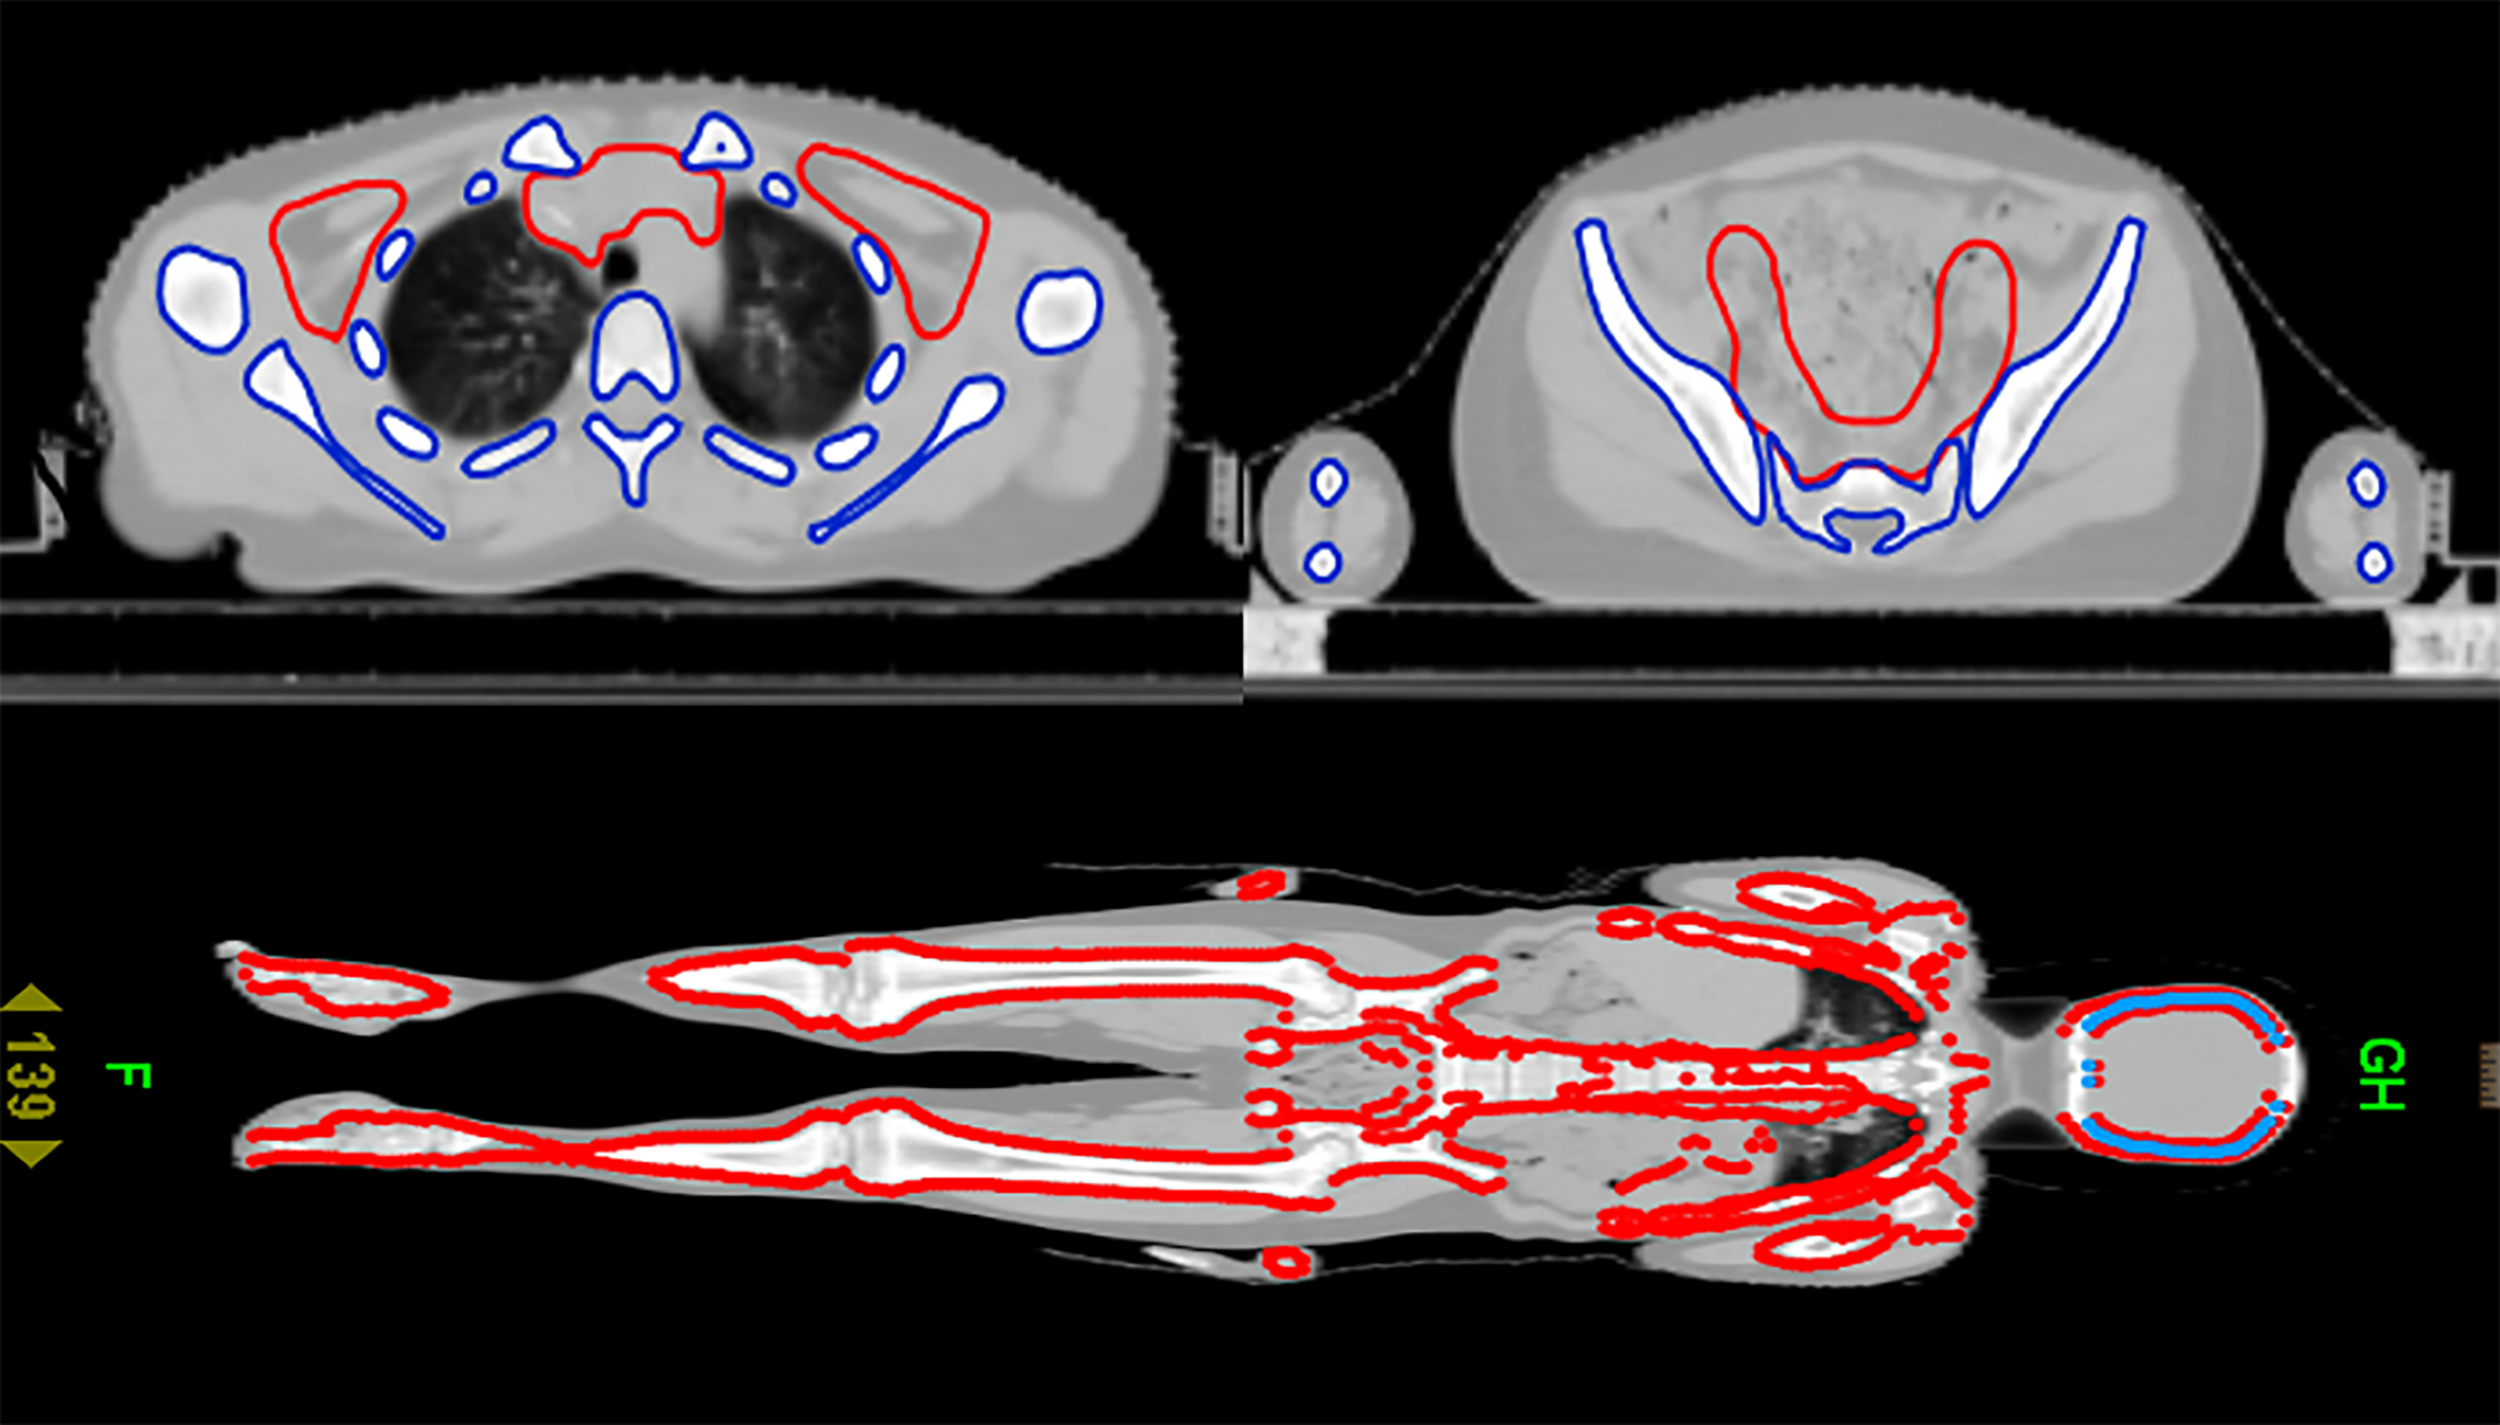

After CT scanning, the data were transmitted to the Varian TPS planning system for target and organ delineation. TBI target definition: subtract all human tissues from the lens and bilateral lungs. The target area of TMLI is defined as total bone marrow and all lymph nodes, including the spleen, brain and testes. Total bone marrow includes skull, mandible, humerus, scapula, clavicle, sternum, vertebra, rib, hip, femur, limb bone, etc. Lymph nodes include cervical lymph nodes, mediastinal lymph nodes, supraclavicular lymph nodes, and inguinal lymph nodes, etc. Organs at risk include the lens, lung, heart, kidney, intestine, liver, etc. The target area for TMLI is delineated, as shown in Figure 1. A CTV uniformly expanded by 5 mm is defined as the PTV.

Figure 2 Cross-sectional dose distribution and coronal dose distribution of TMLI based on HT (12 Gy).